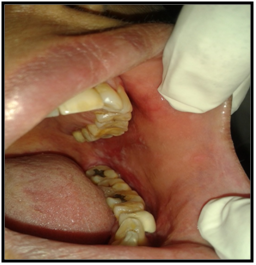

On intraoral examination, diffuse lesions in the form of erythematous areas were seen interspersed within white keratotic areas present all over the facial aspect of gingiva (Figure 2) and more posteriorly on the buccal mucosae bilaterally (Figure 3). Left buccal mucosa showed a white erythematous patch measuring approximately 2x2.5cms extending anteroposteriorly from the area adjacent to mandibular first molar to the retro molar pad area and superior inferiorly from the line of occlusion to the upper and lower lingual vestibule. White radiating striae (wickhamstriae) were present with an interspersed erythematous patch. Right buccal mucosa showed a more extensive lesion measuring approximately 2.5x3cms extending anteroposteriorly from the region adjacent to mandibular canine to the retromolar pad area and superioinferiorly from the upper gingiva buccal sulcus to the lower gingivobuccal sulcus and the alveolar mucosa. Borders of the lesion appear irregular and ill defined. On palpation, the lesions appeared to be tender. The surface of the lesions were rough and non scrapable with no induration noted.

Figure 2The Lesion on the Right and Left Buccal Mucosae.